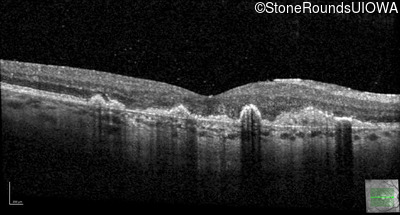

This 43 year old woman has experienced a gradual reduction in her central vision for the past 3 years.

| Malattia Leventinese | EFEMP1 | Arg345Trp CGG>TGG | AD |